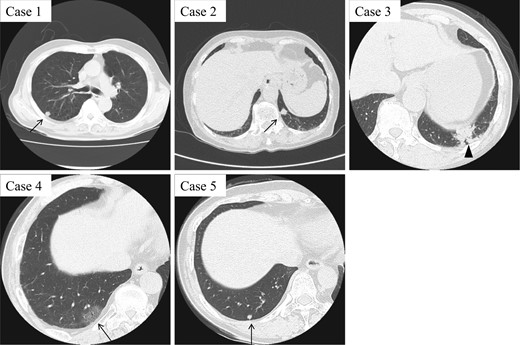

CT findings of five CMPT cases. While Cases 1, 2 and 5 present with small peripheral pulmonary nodules around 10 mm in diameter, Case 4 shows a ground-grass opacity pattern (arrow). Case 3 with mucinous colloid adenocarcinoma exhibits an irregular consolidation-like lesion, which is highly suggestive of lung cancer (arrowhead).

A 66-year-old man with a 45 pack/year smoking history was referred to our hospital with abnormal chest shadow. Chest computed tomography (CT) findings revealed a 10-mm peripheral right lung nodule (Fig. 1). Because frozen sections of the tumor presented borderline lesions with mucinous cystic neoplasm, right upper lobectomy was carried out. Histological findings showed low-grade malignant tumor with ciliated columnar cells and goblet cells (Fig. 2), resulting in a final diagnosis of CMPT. No recurrence has been noted during a 58-month follow-up.

Patient 2

An 82-year-old woman with no smoking history was admitted to our hospital due to abnormal chest shadow. Chest CT findings revealed a 10-mm peripheral nodule in the left S10 segment (Fig. 1). Because lung cancer was strongly suspected, mediastinoscopy followed by thoracoscopic partial resection of the tumor was performed. Frozen sections of the nodule revealed no evidence of malignancy, and CMPT was suspected, confirmed by histological diagnosis (Fig. 2). The patient remained free of recurrence after 55 months.

Patient 3

A 77-year-old man with a 57-pack-year smoking history had an abnormal shadow on routine medical check-up in the left lower lobe (Fig. 1). Lung cancer was strongly suspected, and thoracoscopic left lower lobectomy was performed. Adenocarcinoma was suspected at intraoperative histological consultation, with low-grade malignant tumor including CMPT a possibility. Postsurgical histological findings revealed a transitional or mixed tumor of mucinous colloid adenocarcinoma and CMPT 45 mm in size (Fig. 2). The patient was given oral tegafur-uracil as adjuvant chemotherapy, suspended because of drug toxicity after 6 months. Neither local recurrence nor distant metastasis has been noted at 48 months.

Patient 4

A 70-year-old man with a 92-pack-year smoking history as well as a history of asbestos exposure visited our hospital with a 30-mm peripheral ground-grass opacity (GGO) in the right lower lobe (Fig. 1). Thoracoscopic partial resection of the tumor was performed, and intraoperative frozen section investigation revealed CMPT, which was confirmed by postoperative histological analysis. The tumor showed proliferation of the mucinous epithelium at 15 mm in the subpleural area (Fig. 2). The patient remained relapse-free at 19 months.

Patient 5

A 67-year-old woman was referred with a growing peripheral small lung nodule. She had never smoked but had a medical history of bronchial asthma and eosinophilic pneumonia treated with oral corticosteroid. Chest CT revealed remaining lung nodules with pleural indentation in the S10 segment of the right lung (Fig. 1). Thoracoscopic partial resection was conducted, and pathological diagnosis was CMPT 5 mm in diameter (Fig. 2). The patient remained free of recurrence 28 months postoperatively.